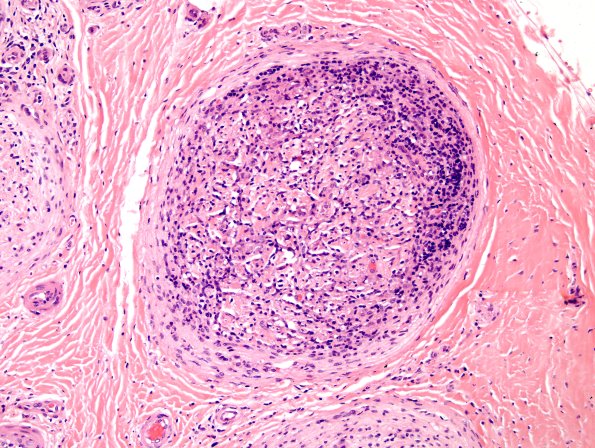

Washington University Experience | PERIPHERAL NEUROPATHY | 10 INFECTION | 4 Leprosy – Tuberculoid | 2A3 Leprosy, tuberculoid (Case 2) H&E 2

2A3,4 There are prominent lymphocytic infiltrates at the margins of many fascicles. Axons have been lost in great numbers. (H&E)